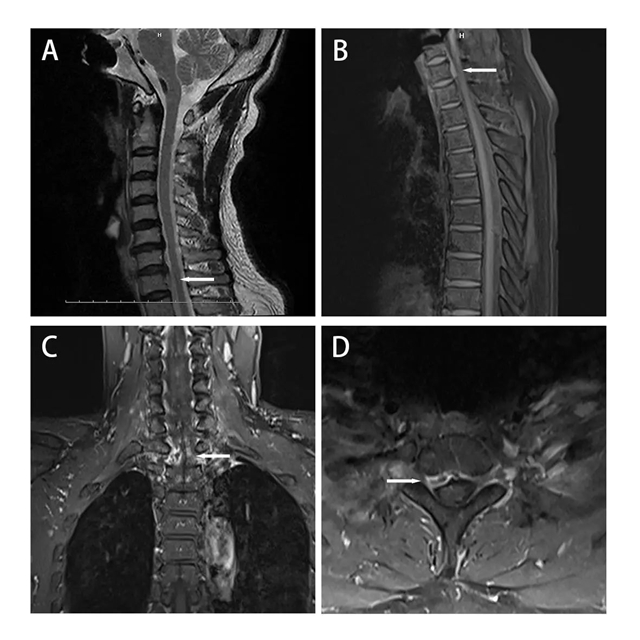

术前MRI表现

为啥叫“雷区”?因为在这个狭小的区域,有给全身供淋巴液的“生命管道”胸导管、掌管发声的喉返神经... 密密麻麻全是重要结构!

如果按照传统手术方案,为了摘这个“炸弹”,可能得开胸劈骨!